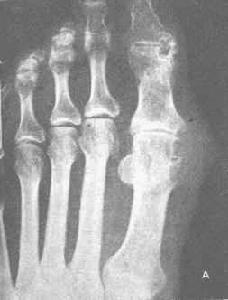

中老年男性肥胖者,突然反復發作的單個跖趾、跗跖、踝等關節紅腫劇痛,可自行緩解及間歇期無癥狀者,應首先考慮到痛風性關節炎;同時合并高尿酸血癥及對秋水仙堿治療有效者可診斷為痛風;滑液或滑膜活檢發現尿酸鹽結晶者即可確診。